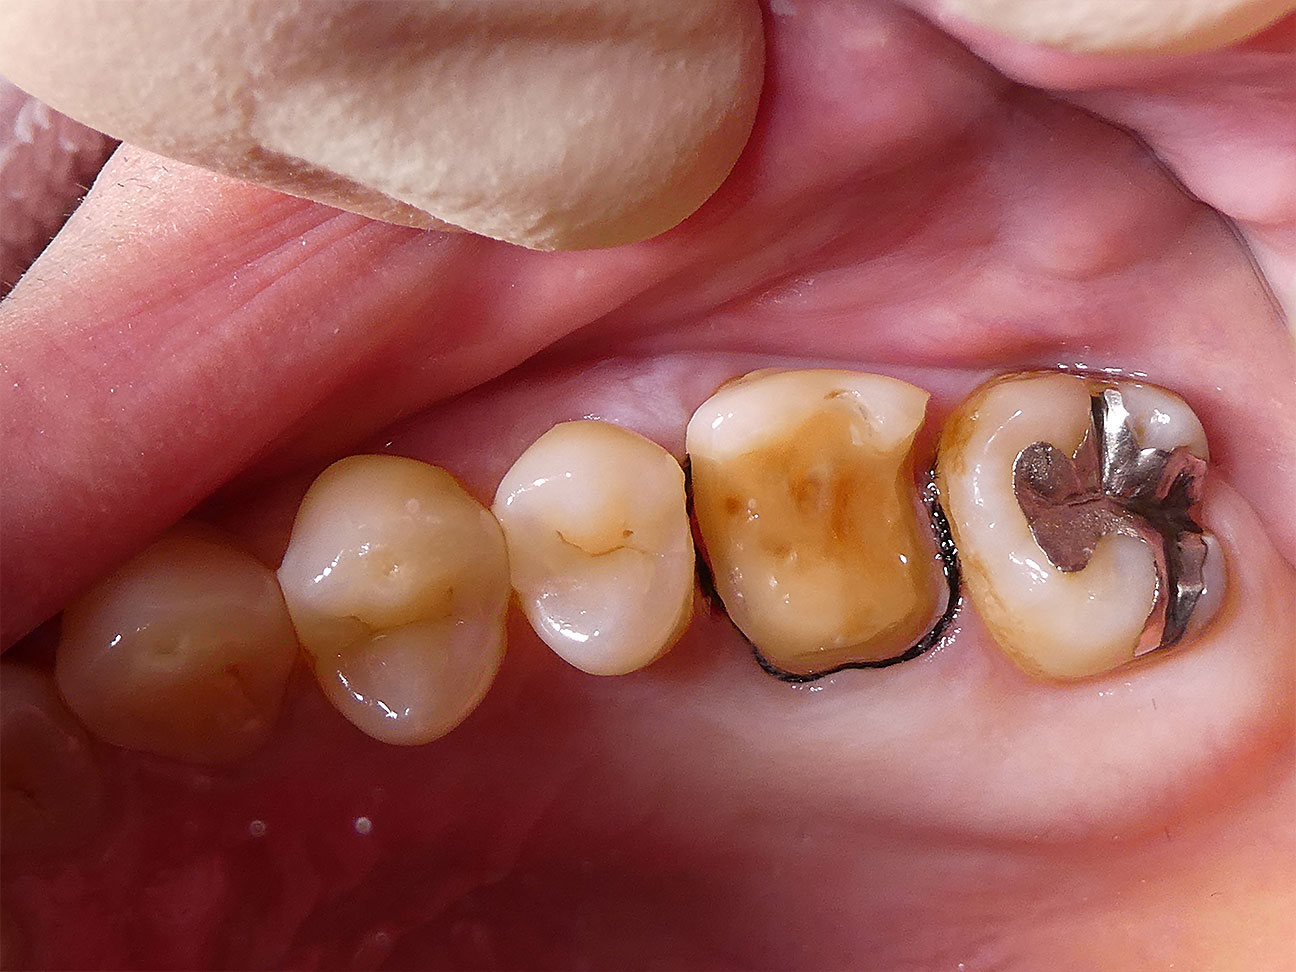

STEP4 形成と圧排

虫歯を丁寧に取りきった後の歯です。今回は力の加わる奥歯であり、隣りあう歯にも回り込む形で詰めものをするため、ジルコニア製で強度の高いアンレーという形態の詰めものを選択しています。そのため歯肉圧排という方法で歯と歯茎の境目をしっかりと分け歯型(印象)を採得しました。